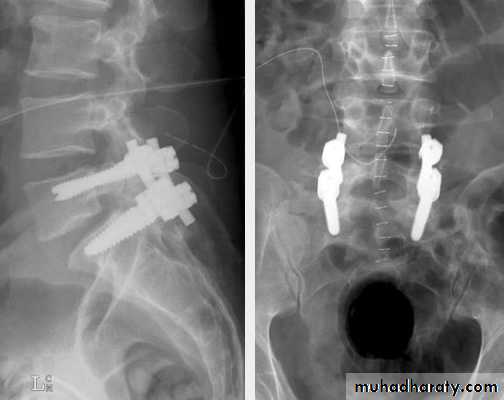

The surgery is posterior or anterior intervertebral body fusion.